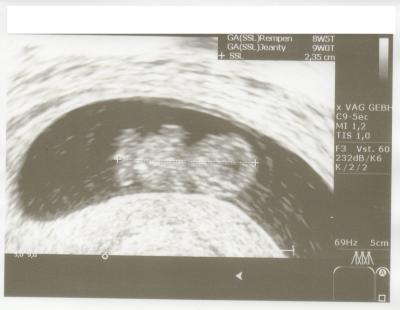

Hallo ihr Lieben! Wir waren gestern beim FA und haben den kleinen Krümel gesehen. Es war das Schönste was ich je gesehen habe :) Hat schon kräftig gezappelt und das Herzchen schlägt auch noch super. Der Fa ist zufrieden und alles soll toll sein. Da sind wir sehr glücklich drüber. Eine kleine Wolke gibt es allerdings und ich weiss nicht was ich davon halten soll... Bin ab HEUTE in der 11 SSW - also laut Arzt 10+1. Unser kleines Wunder ist aber erst ca 2,5 cm groß. :s Der Fa meinte, dass man das mal beobachten muss weil das Kleine eine Woche kleiner ist als üblich. Muss ich mir da jetzt Sorgen machen?! Liebe Grüße

hallo lass die ned verunsichern i bin jetzt 10+1 und wurm ist 2,6 cm gr.laut klinik gestern und es ist alles soweit okay mim wurm...man kann es eh erst genau messen und feststellen in der 12 wo etc meinten die und auf dinem bild steht ja 2,35 em und evtl hat sich euer würmchen grad gedreht war vor einer wo a bei meinem fa so...drück euch die daumen und mach die ned verrückt.. lg sue